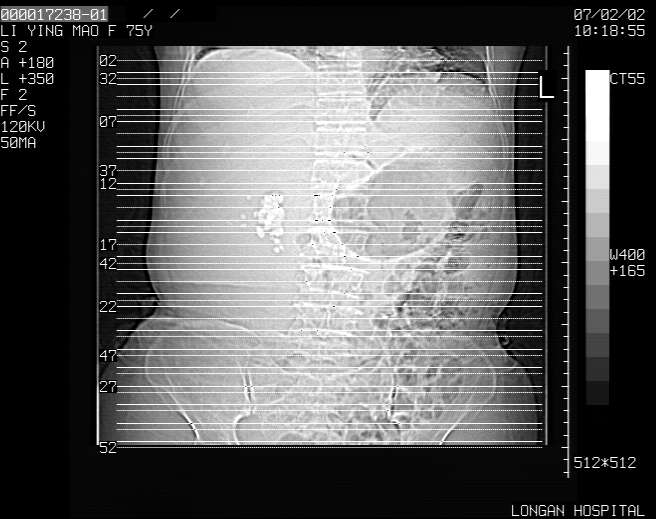

以下是引用dyqct在2007-2-10 8:53:00的发言:[br]考虑:1、肝脏多发囊肿[br] 2、左肾囊肿,右肾多发结石并积水。[br] 3、右胸少量积液。[br] 4、右肾周包裹性积液或淋巴管瘤(有见缝就钻的征象、薄隔、小结节状钙化)?[br] 5、腰椎动脉瘤样骨囊肿?[br] [br] [br]